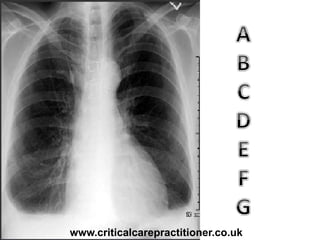

TECHNICALS

AIRWAY

BONES

cARDIAC

DIAPHRAGM

GASTRIC BUBBLE

EQUAL LUNG FIELDS